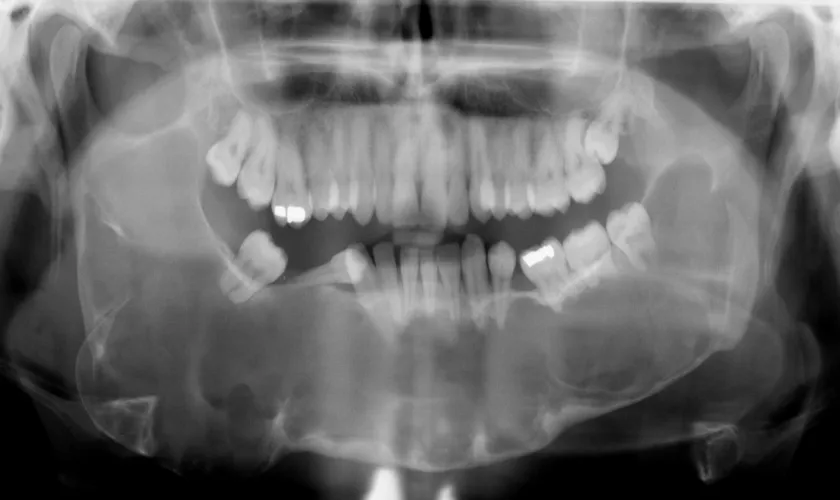

We begin with a thorough digital analysis using advanced CBCT imaging to precisely map the tooth's fusion, root structure, and the surrounding bone, guaranteeing an accurate diagnosis.

Diagnosis typically involves a thorough clinical examination and imaging studies, such as X-rays or CBCT scans. These tools help visualize the tooth's position and its relationship with the jawbone. Early diagnosis is key to effective treatment.